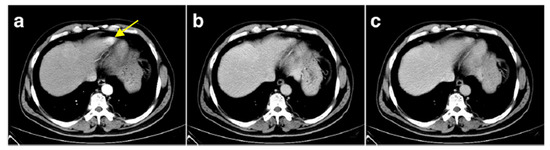

Splenosis arises from traumatic splenic rupture or splenectomy. Splenosis is missing some splenic characteristics such as smooth muscle elements. Due to the trapping of the released spleen cells by the pre-portal system capillaries, intrahepatic splenosis is rare. Figure 6 shows a contrast-enhanced CT in a patient who underwent a splenectomy five years before following a high-altitude accident. The CT showed an intrahepatic mass in the left apex of the liver, evidenced as splenic cell tissue after surgical resection [55].

Figure 6. Contrast enhanced liver CT. (ac): Arterial, portal, and equilibrium phase, respectively (reprinted from [55] under the license CC BY 4.0). Yellow arrow: left liver apex mass which re-enhanced contrast during the arterial phase.